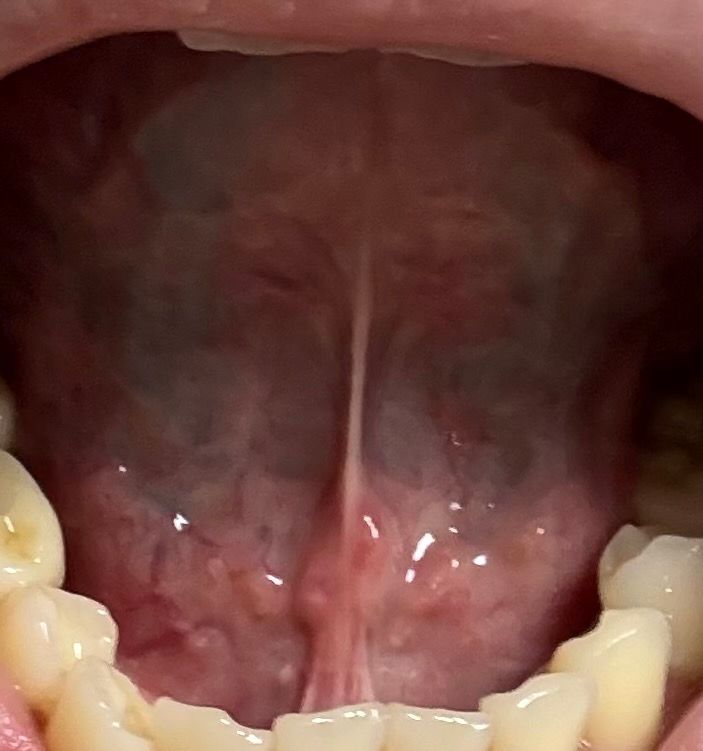

혀아래에 어느순간부터 하나둘 나더니 번지는것처럼 나는데 이거 뭔가요? Hpv 6번 보유하고 있는데 그 영향인가요? 잘 아시는분.. 아프거나 하는 통증은 없습니다.55글자 더 채워주세요.

혀 아래에는 보통 저렇게 우둘투둘한 구조물들이 많기는 합니다. 질문자님 눈에 갑자기 띄어서 뭔가 생겨났다고 생각하실수도 있긴 한데요. 만약 그런것이 아니라 실제로 원래 없던 것들이 갑자기 생겨나기 시작해서 번져나가는 것이라면 사진만으로는 알기 힘들고 구강내과나 구강외과 전문의 선생님께 찾아가서 생검을 해보시거나 검사를 해보시는게 가장 정확 합니다.

HPV 6형은 저위험군 HPV로 혀아래, 입안, 인후등에 생길수 있고, 통증은 없고 번져 보일수 있습니다. 따라서 계속 지속되고 번지는 경우에는 치과나 이비인후과 진료를 권합니다.